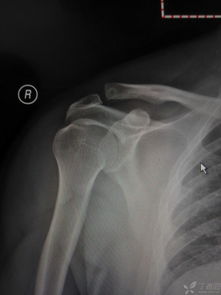

(1)肩鎖關(guān)節切開(kāi)復位克氏針固定術(shù):此法適用于Ⅱ型脫位病例。病人取仰臥位,患肩墊高,常規消毒、鋪巾,頸路肌間溝麻醉生效后,沿鎖骨外端并繞過(guò)肩峰做切口,長(cháng)約8~9cm(圖4),骨膜下將斜方肌和三角肌附著(zhù)處切開(kāi)分離,顯露肩鎖關(guān)節,清除碎骨片及關(guān)節間組織,將上臂向上推,并同時(shí)向下壓鎖骨外端,使肩鎖關(guān)節復位,兩枚克氏針交叉穿過(guò)肩鎖關(guān)節固定;修復肩鎖韌帶、關(guān)節囊和喙肩韌帶,剪除多余的克氏針,將遠端彎成鉤狀埋入皮下,以防克氏針發(fā)生移位、滑脫,再將斜方肌和三角肌邊緣在鎖骨及肩峰處褥式縫合,最后縫合皮膚,術(shù)后用三角巾懸吊傷肢4~6周。

如用此方法治療Ⅲ型肩鎖關(guān)節脫位,應在上述操作的同時(shí),經(jīng)鎖骨至喙突加1枚螺絲釘固定,使兩骨靠近,以利喙鎖韌帶修復。術(shù)后4~6周拔除鋼針,1年后取出螺絲釘(圖5)。